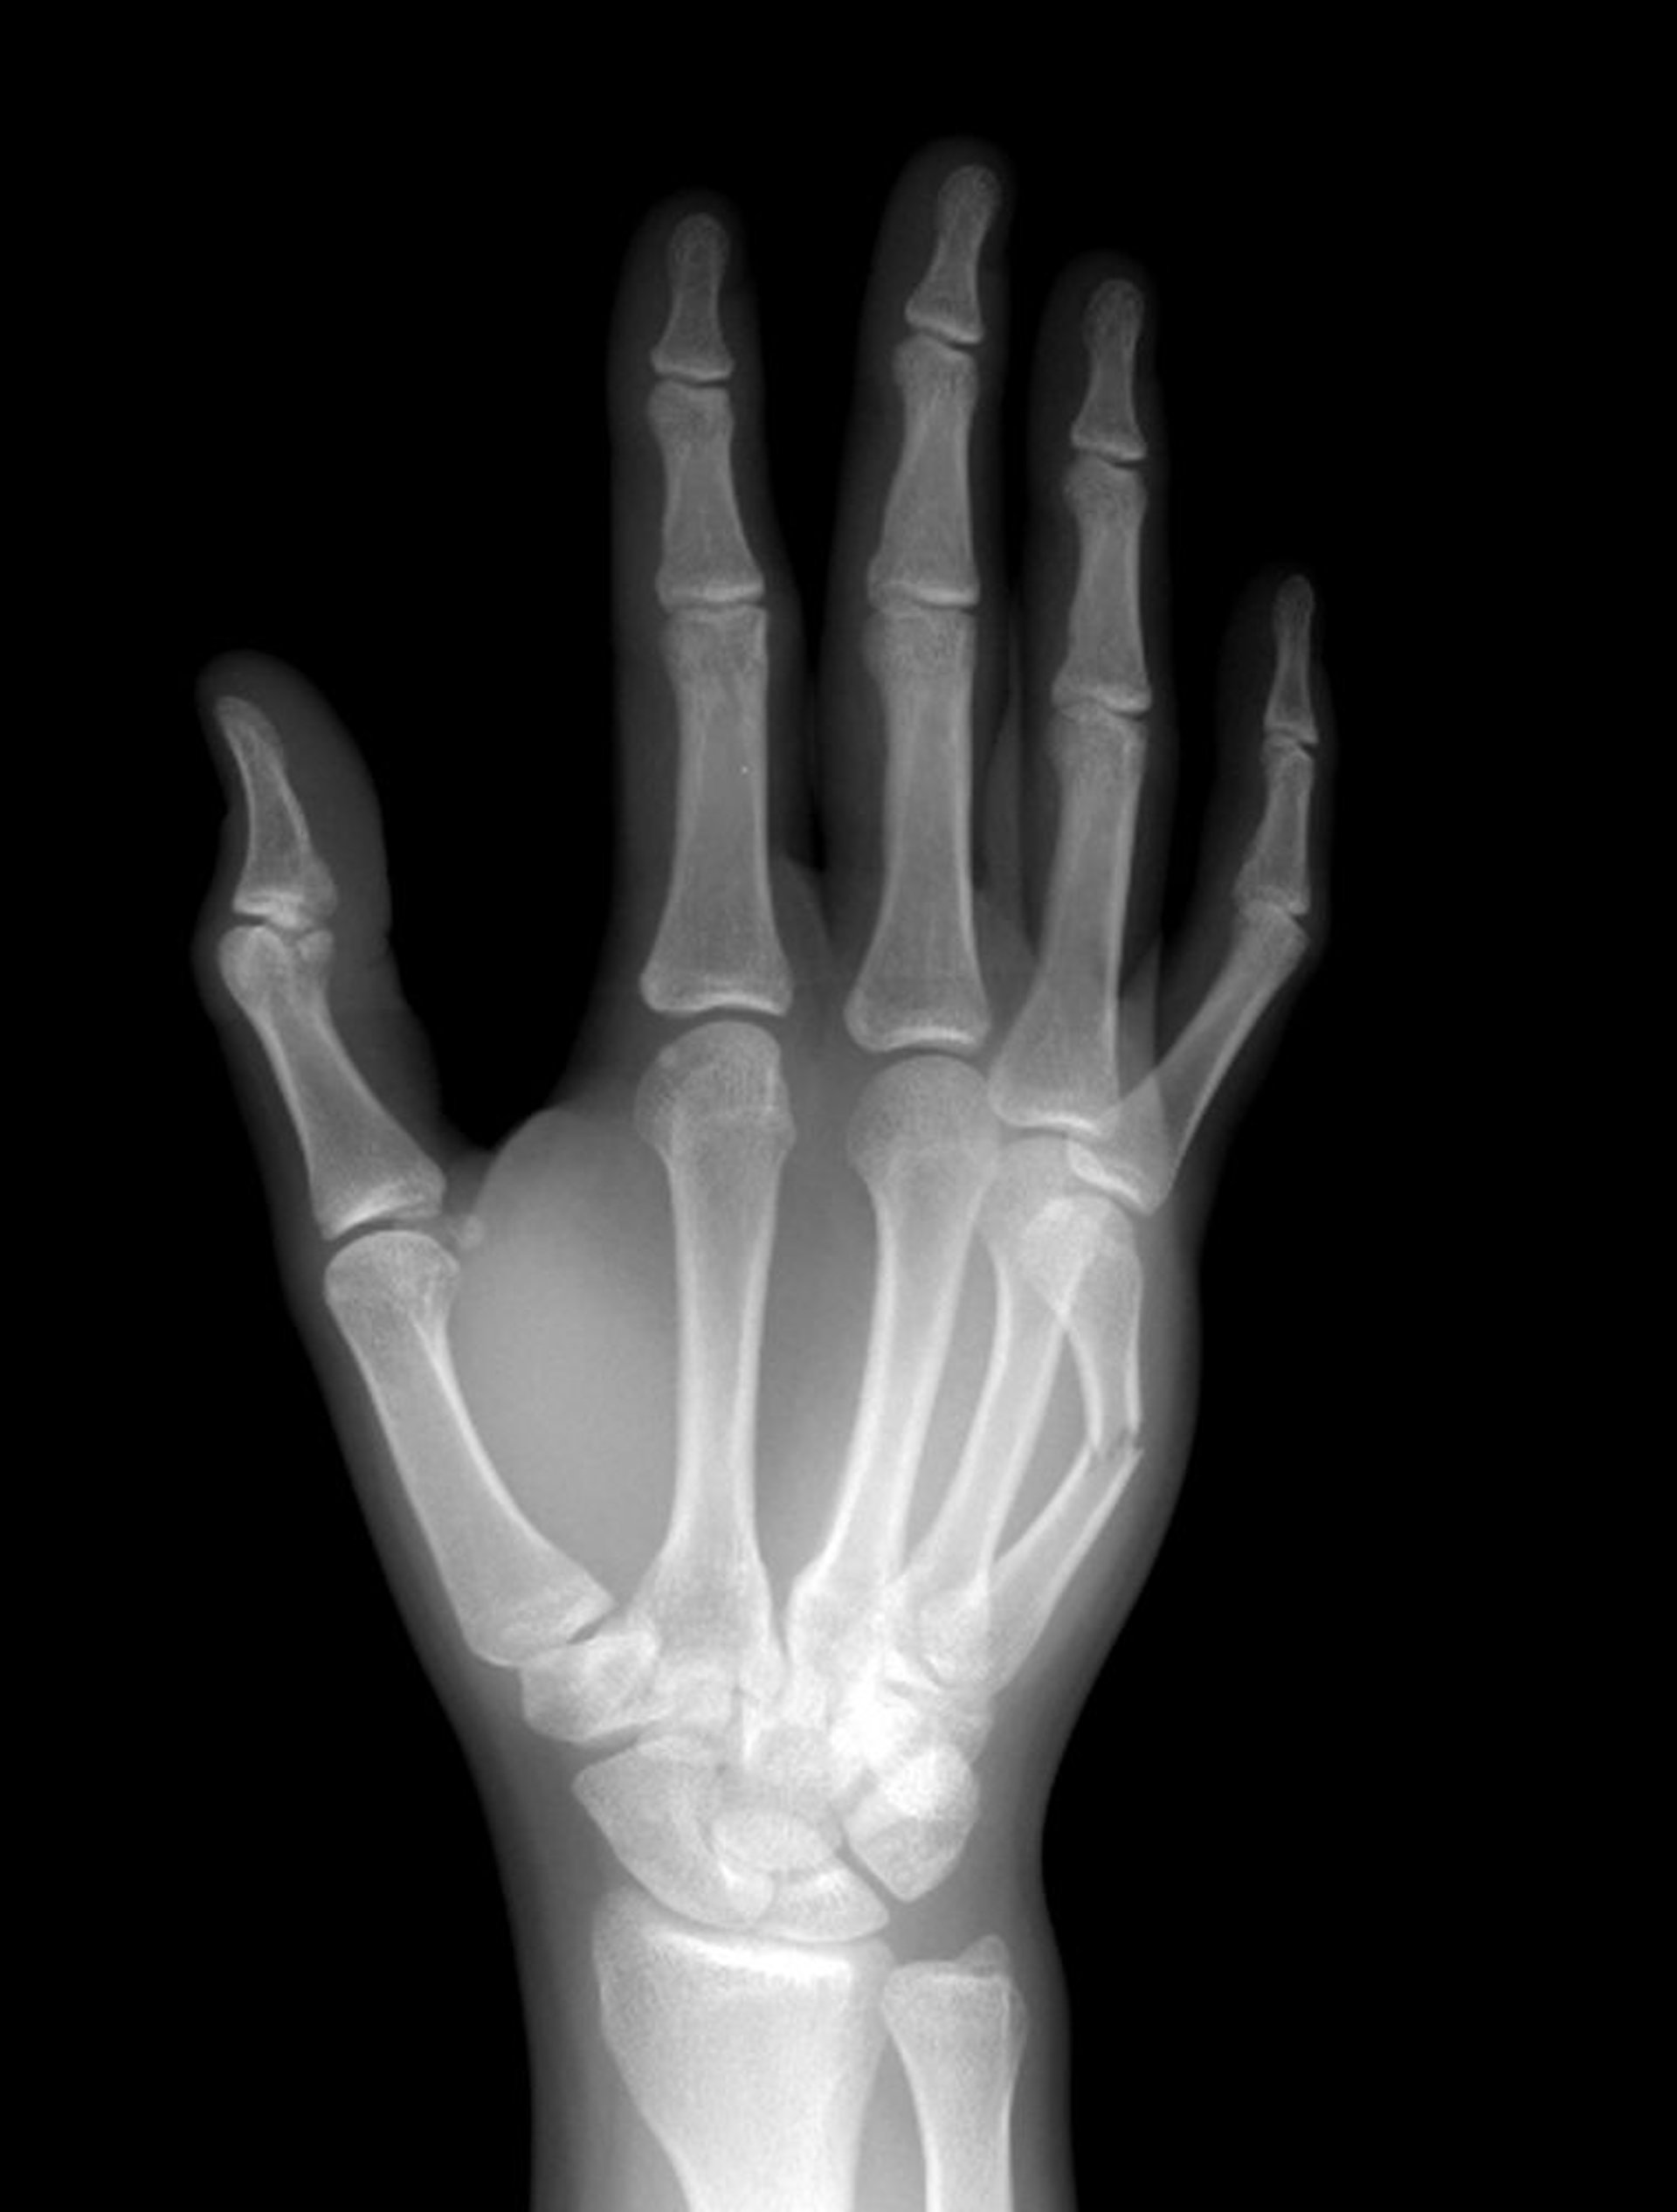

Fracture du col des métacarpiens

Le col du 5e os métacarpien est fracturé à mi-diaphyse.

LIVING ART ENTERPRISES, LLC/SCIENCE PHOTO LIBRARY